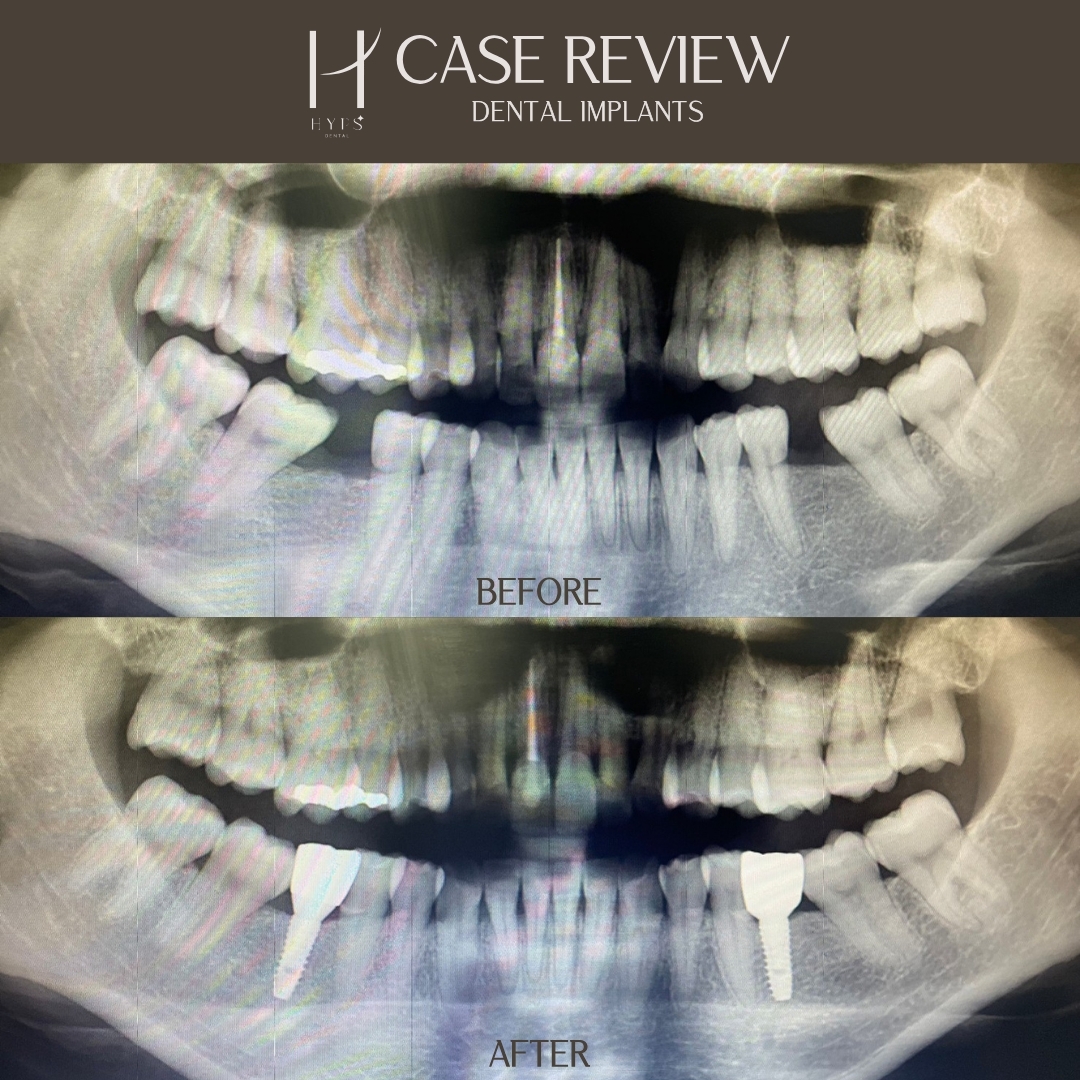

Dental Implant

You can track our dental clinic’s outcomes through this channel,

which serves as both an example and a reference for making treatment decisions.